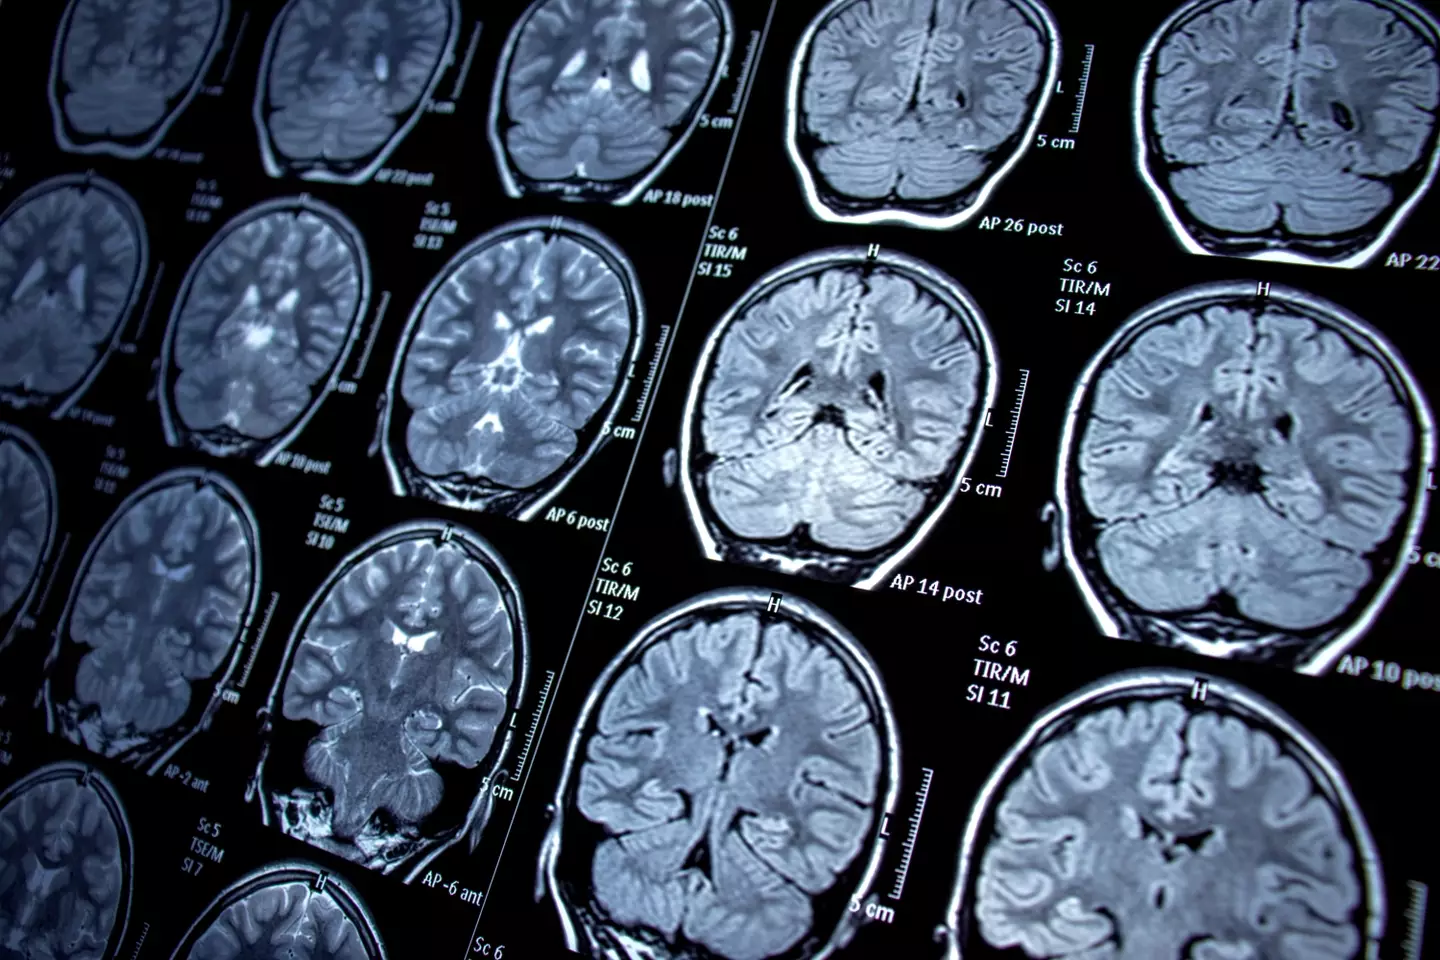

According to a 2021 study, ‘sexual pleasure is a cognitive experience based on the reciprocal relationship between bodily physiology and nervous system function’.

In short: we get off because our brain is in sync with our nerves.

It went on to share that ‘specific brain activity stimulates physiological responses in the genital system that in turn generates sensory nerve feedback to the brain, whose neurons generate pleasure'.

So, orgasms only happen due to this sensory feedback from the brain.